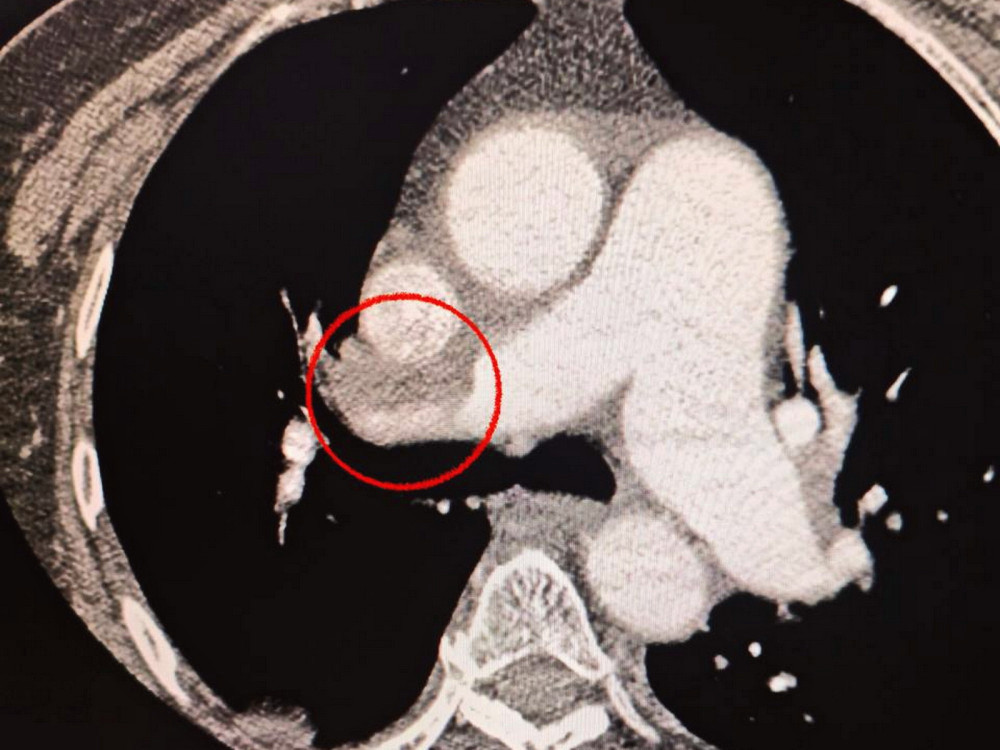

Лікарі також помітили, що жінка має труднощі з диханням, тому було вирішено додатково провести обстеження легенів. Виявилося, що у неї також є тромбоемболія легеневої артерії.